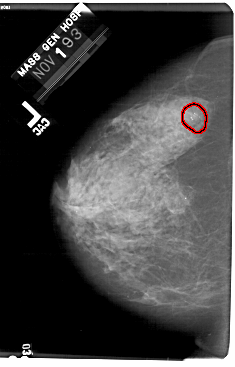

A_1732_1.RIGHT_MLO

FILE: A_1732_1.LEFT_CC.OVERLAY

TOTAL_ABNORMALITIES 1

ABNORMALITY 1

LESION_TYPE CALCIFICATION TYPE AMORPHOUS DISTRIBUTION CLUSTERED

ASSESSMENT 2

SUBTLETY 4

PATHOLOGY BENIGN

TOTAL_OUTLINES 1

BOUNDARY